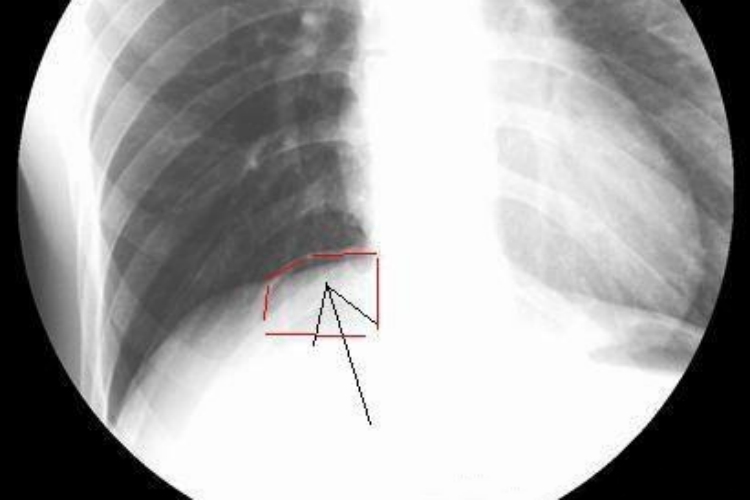

肠穿孔常表现为持续性的腹痛,腹部X线可发现膈下有游离气体,单侧或双侧,表现为线条状、新月状的透亮影,边缘清楚。

肠穿孔的主要X线征象为腹腔内游离气体,立位X线检查可见膈下游离气体,单侧或者双侧,表现为线条状、新月状的透亮影,边缘清楚。右侧透亮影的下缘为致密光滑的肝脏影,左侧新月状透亮影下内为胃泡影,外下方为脾脏影。大量气腹时可见双膈位置升高,内脏向下、内移,从而衬托出肝、脾、胃等脏器的外形轮廓。